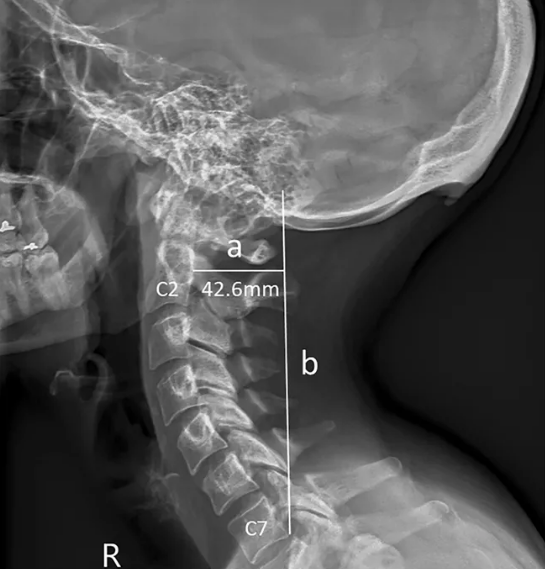

Avustralya’daki Sunshine Coast Üniversitesi’den bilim adamları Dr. David Shahar ve Prof. Mark Sayers, 18-30 yaş arasındaki 218 kişinin röntgen çekimlerini inceledi. Yapılan araştırmalar sonucu röntgen çekilen kişilerin neredeyse yarısının kafatası şeklinin yoğun cep telefonu ve tablet kullanımına bağlı olarak ‘değiştiği’, boynuzumsu bir çıkıntıya benzediği belirtildi.

Yapılan araştırmaya göre, gününün büyük kısmında teknolojik aletlere kafasını eğerek bakan gençlerin, kafatasındaki oksipital kemik denen bölge, görünür şekilde belirginleşmeye başlıyor.

Her 4 gençten birinde görülen bu durum, dijital ekranlar karşısında geçirilen süreyle ilgili endişelere bir yenisini daha ekliyor.